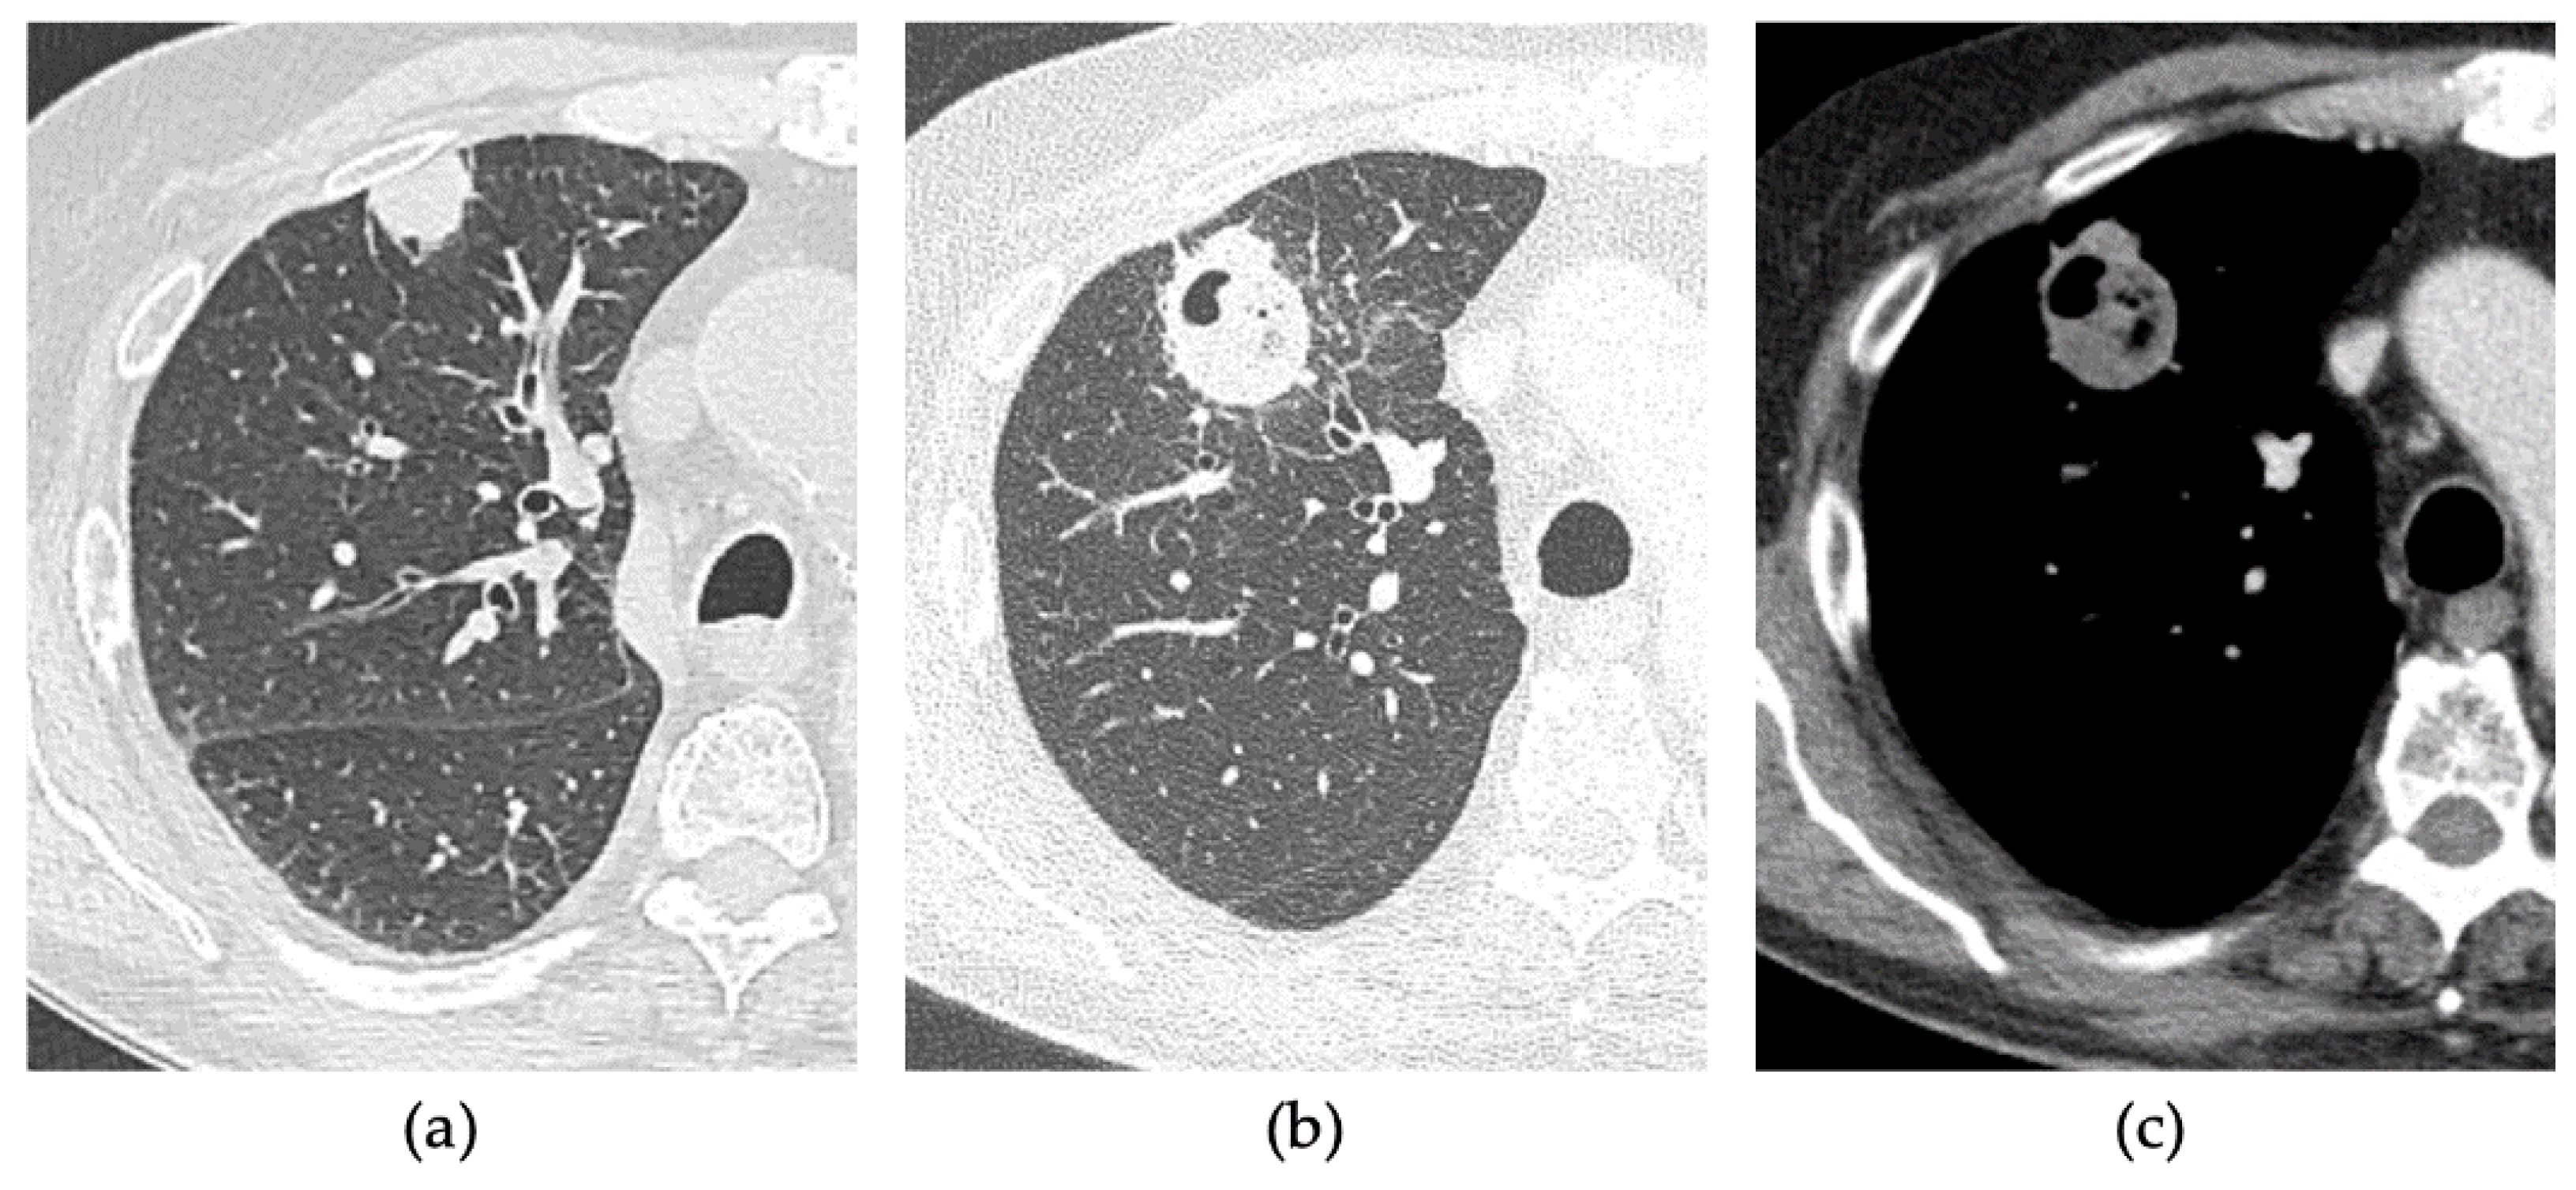

2.2. Procedure

2.3. CT Follow-Up